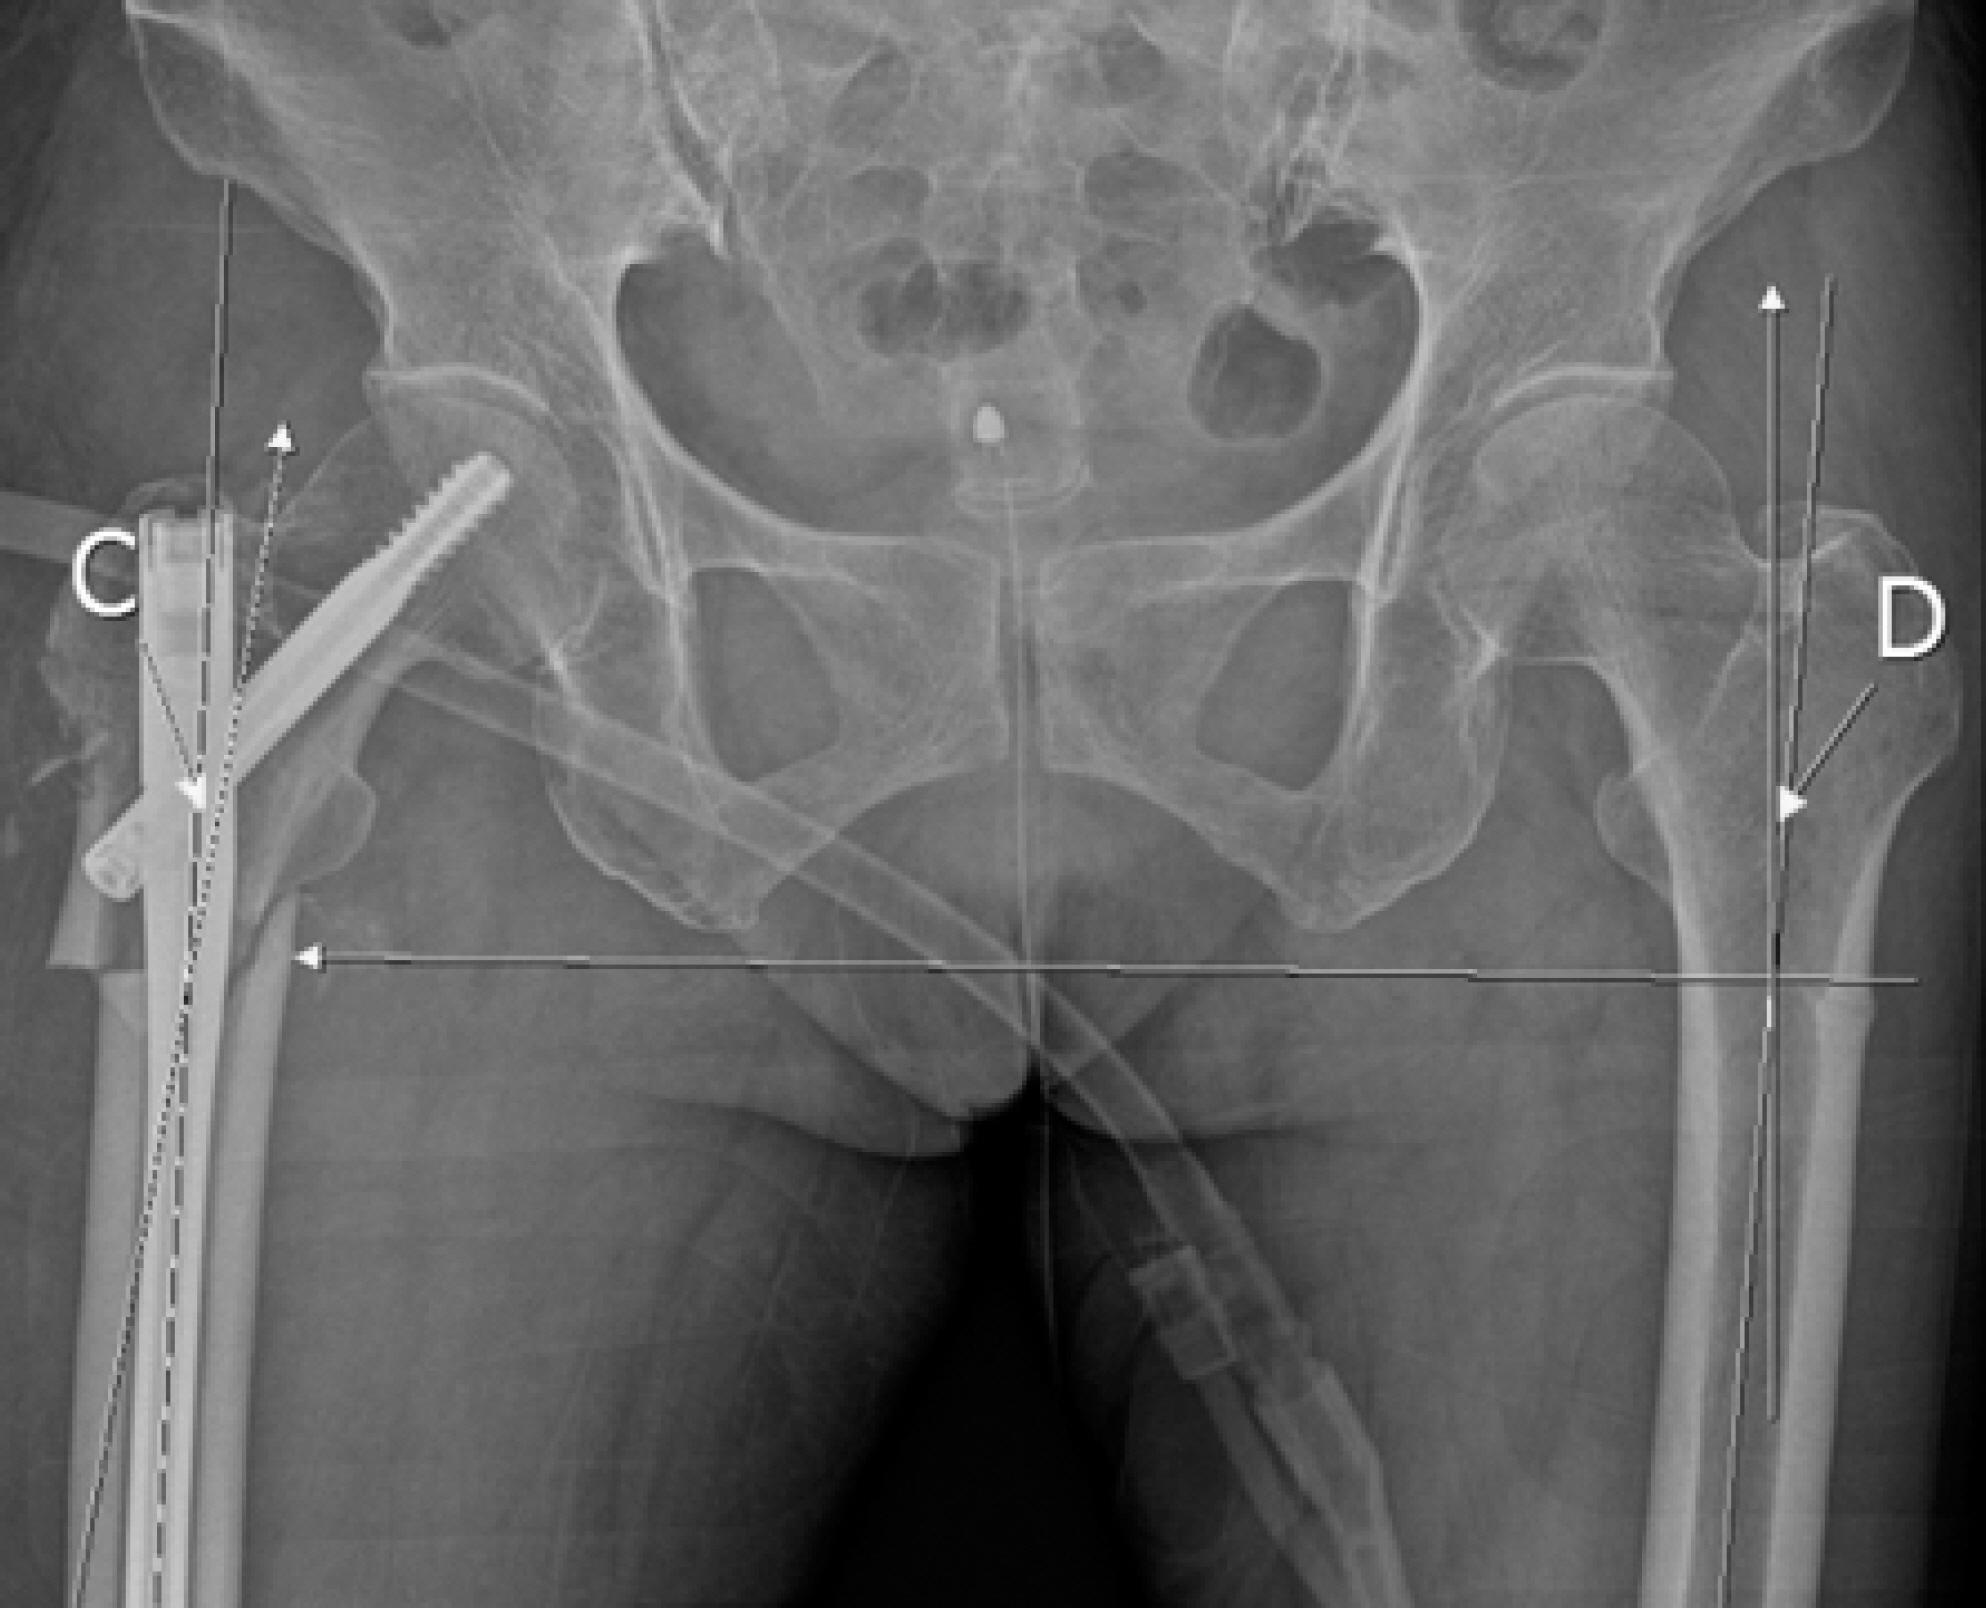

Fig. 2.

In the coronal plane, the angle that the proximal and distal fragments make on the same line as the fracture line based on the unaffected side (letter ‘C’), The angle that the distal and proximal fragments make on the basis of the fracture site of the affected side (letter ‘D’). If C-D is 0: neutral, (–): valgus, (+): varus.